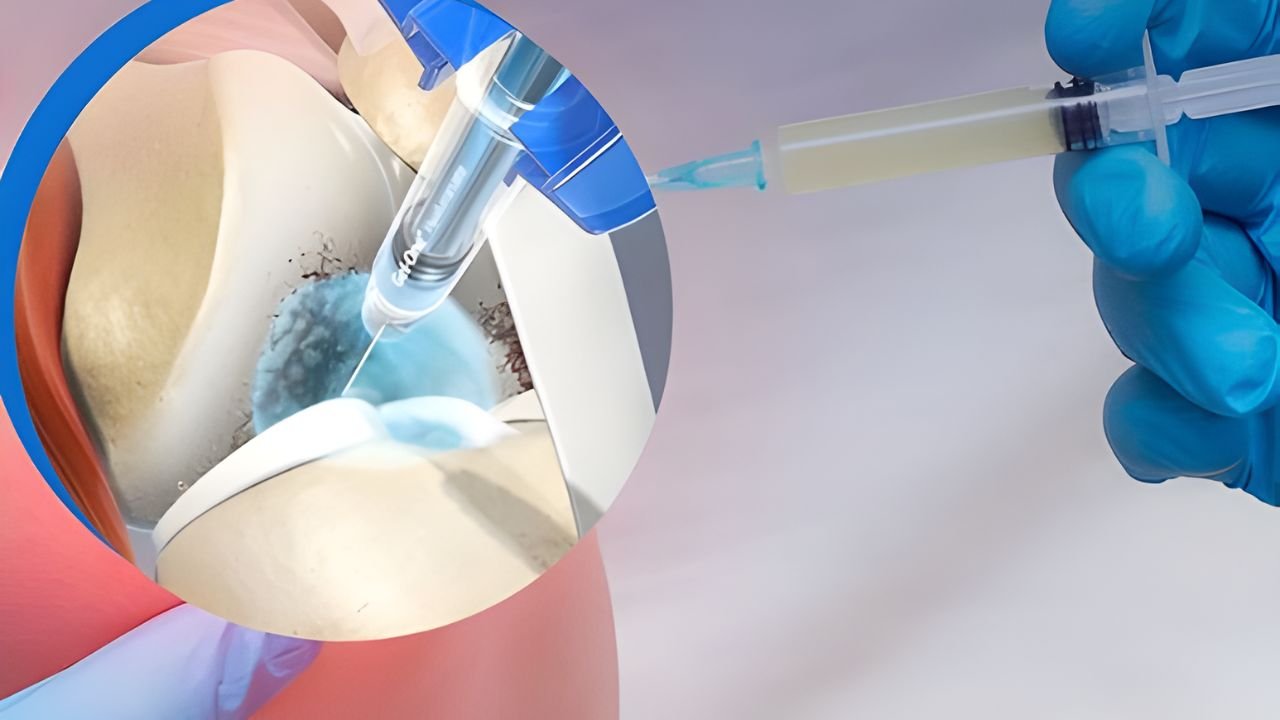

A dor articular, especialmente no joelho decorrente da artrose, é um dos maiores obstáculos à mobilidade e independência dos pacientes.

A dor articular, especialmente no joelho decorrente da artrose, é um dos maiores obstáculos à mobilidade e independência dos pacientes.

A dor articular, especialmente no joelho decorrente da artrose, é um dos maiores obstáculos à mobilidade e independência dos pacientes.

Não. Nossa filosofia prioriza procedimentos minimamente invasivos. A grande maioria dos casos é resolvida com intervenções percutâneas (sem cortes), terapias medicamentosas ajustadas, ondas de choque ou infiltrações guiadas. A cirurgia é considerada apenas quando estritamente necessária.

O conforto do paciente é prioridade. Os procedimentos são realizados com anestesia local e, quando necessário, sedação leve. A maioria dos pacientes relata alívio imediato ou desconforto mínimo durante a aplicação, retornando às suas atividades em pouco tempo.